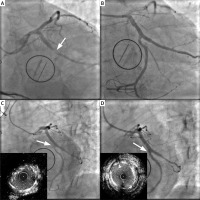

Angiography. A – Angiogram view (LAO/CAUD): white arrow shows occlusion of the left circumflex artery (June 2020). B – Post-stenting angiography (June 2020). C – Control coronarography after 4 months: arrow shows in-stent restenosis + IVUS view (September 2020). D – Final result after additional stenting + final IVUS (September 2020)

We present a case of a 57-year old man with a medical history of hypertension, coronary artery disease, heart failure, and hyperlipidemia. In June 2020 due to endocarditis the patient underwent valve surgery which required implantation of a mechanical valve (SJM 29). The intervention was complicated by postprocedural myocardial infarction (MI) expressed as ST segment elevation. The Heart Team convened ad hoc in the catheterization laboratory and decided on percutaneous coronary intervention (PCI). Coronary angiography revealed total occlusion of the left circumflex artery (Cx) at the origin of the large first marginal obtuse artery (Mo), which additionally presented proximal stenosis (Figure 1 A). The coronary angiography performed before the operation showed no signs of coronary atherosclerosis in these locations. The surgeon’s description of the operation, together with the coronary angiogram, suggested that the Cx stenosis was associated with annuloplasty suture ligation, which is a rare, but possible complication due to proximity of the Cx and mitral annulus [1–3]. After guidewires crossed the Mo and Cx, predilatation with 2.5 mm and 3.0mm non-compliant (NC) balloons was performed. After the balloons were pulled out, a control contrast injection was made. Cx narrowing appeared again, probably in the place where tissues or stitches caused pressure. Due to recurrent Cx stenosis after ballooning the final decision was made to implant a stent. Using the culotte technique and Guideliner system, two drug-eluting stents (DES) were placed: 2.5 × 26 mm Resolute Onyx in the Cx and after proximal optimization (POT) 4.0 × 18 mm Resolute Onyx in the large Mo. Finally “kissing balloons” inflation with NC 3.0 mm and 4.0 mm balloons was performed and re-POT with the NC 4.0 mm balloon. We obtained a good procedural effect, but still with some pinching in the stent in the area of Cx former amputation (Figure 1 B). Transthoracic echocardiogram showed left ventricular hypokinesia and depressed left ventricular function (ejection fraction between 35% and 40%).

The catheterization showed 90% restenosis in the DES which had been placed in the Cx exactly in the spot of the former amputation (Figure 1 C). After predilatation intravascular ultrasound (IVUS) was used and confirmed in-stent restenosis, after which the 3.0 × 8 mm DES (Resolute Onyx) was chosen and with the T and small protrusion (TAP) technique was placed. For proper stent expansion “kissing balloons” and POT methods with two 4.0 × 6 mm NC balloons were used (Figure 1 D). IVUS showed 8.4 mm minimal stent area (MSA) in double layer stents area in the Cx and proved a good procedural effect.